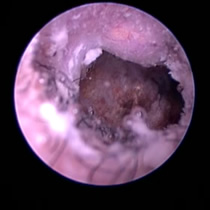

耳ダニ感染後の鼓膜喪失と中耳炎

長く耳ダニに気付かず治療が遅れた猫です。すでに鼓膜を失っており、中耳をきれいに洗浄すると赤い肉芽が確認できました。この肉芽を除去し点耳薬で治療すると改善。鼓膜が全く残っていないため鼓膜の再生は期待できませんが、痛みや痒みもなく元気に過ごしています。